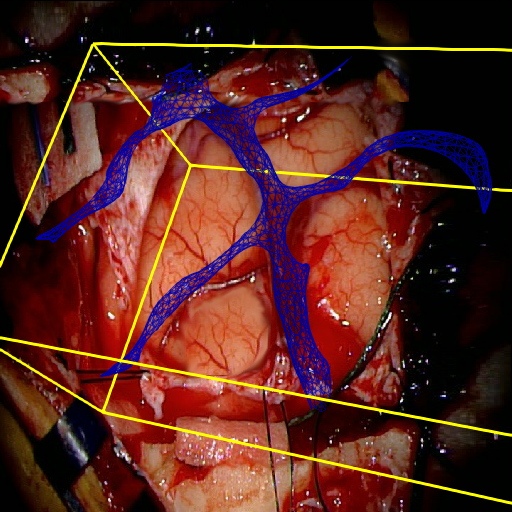

We tested our method retrospectively on 6 clinical datasets from 6 patients (cases) (see Fig. 5). These consisted of preoperative T1 contrast MRI scans and intraoperative images of the brain surface after dura opening. Cortical vessels around the tumors were segmented and triangulated to generate 3D meshes using 3D Slicer. We generated 100 poses for each 3D mesh (i.e.: each case) and used a total of 15 unique textures from human brain surfaces (different from our 6 clinical datasets) for synthesis using . In order to account for potential intraoperative brain deformations [4] we augment the textured projection with elastic deformation [21] resulting in approximately 1500 images per case. The surgical images of the brain (left image of the stereoscopic camera) were acquired with a Carl Zeiss surgical microscope. The ground-truth poses were obtained by manually aligning the 3D meshes on their corresponding images.

Test and Comparison on Clinical Images

We compared our method (Ours) with segmentation-based methods (ProbSEG) and (BinSEG) [7]. These methods use learning-based models to extract binary images and probability maps of cortical vessels to drive the registration. We report in Tab. 1 the distances between the ground truth and estimated poses. Our method outperformed ProbSEG and BinSEG with an average ADD error of mm compared to mm and mm, respectively. Our errors remain below clinically measured neuronavigation errors reported in [4], in which a mm average initial registration error was measured in 15 craniotomy cases using intraoperative ultrasound. Our method outperformed ProbSEG in 5 cases out of 6 and BinSEG in all cases and remained within the clinically measured errors without the need to segment cortical vessels or select landmarks from the intraoperative image. Our method also showed fast intraoperative computation times. It required an average of only milliseconds to predict the pose (tested on research code on a laptop with NVidia GeForce GTX 1070 8GB without any specific optimization), suggesting a potential use for real-time temporal tracking.

Fig. 5 shows our results as Augmented Reality views with bounding boxes and overlaid meshes. Our method produced visually consistent alignments for all 6 clinical cases without the need for initial registration. Because our current method does not account for brain-shift deformation, our method produced some misalignment errors. However, in all cases, our predictions are similar to the ground truth.